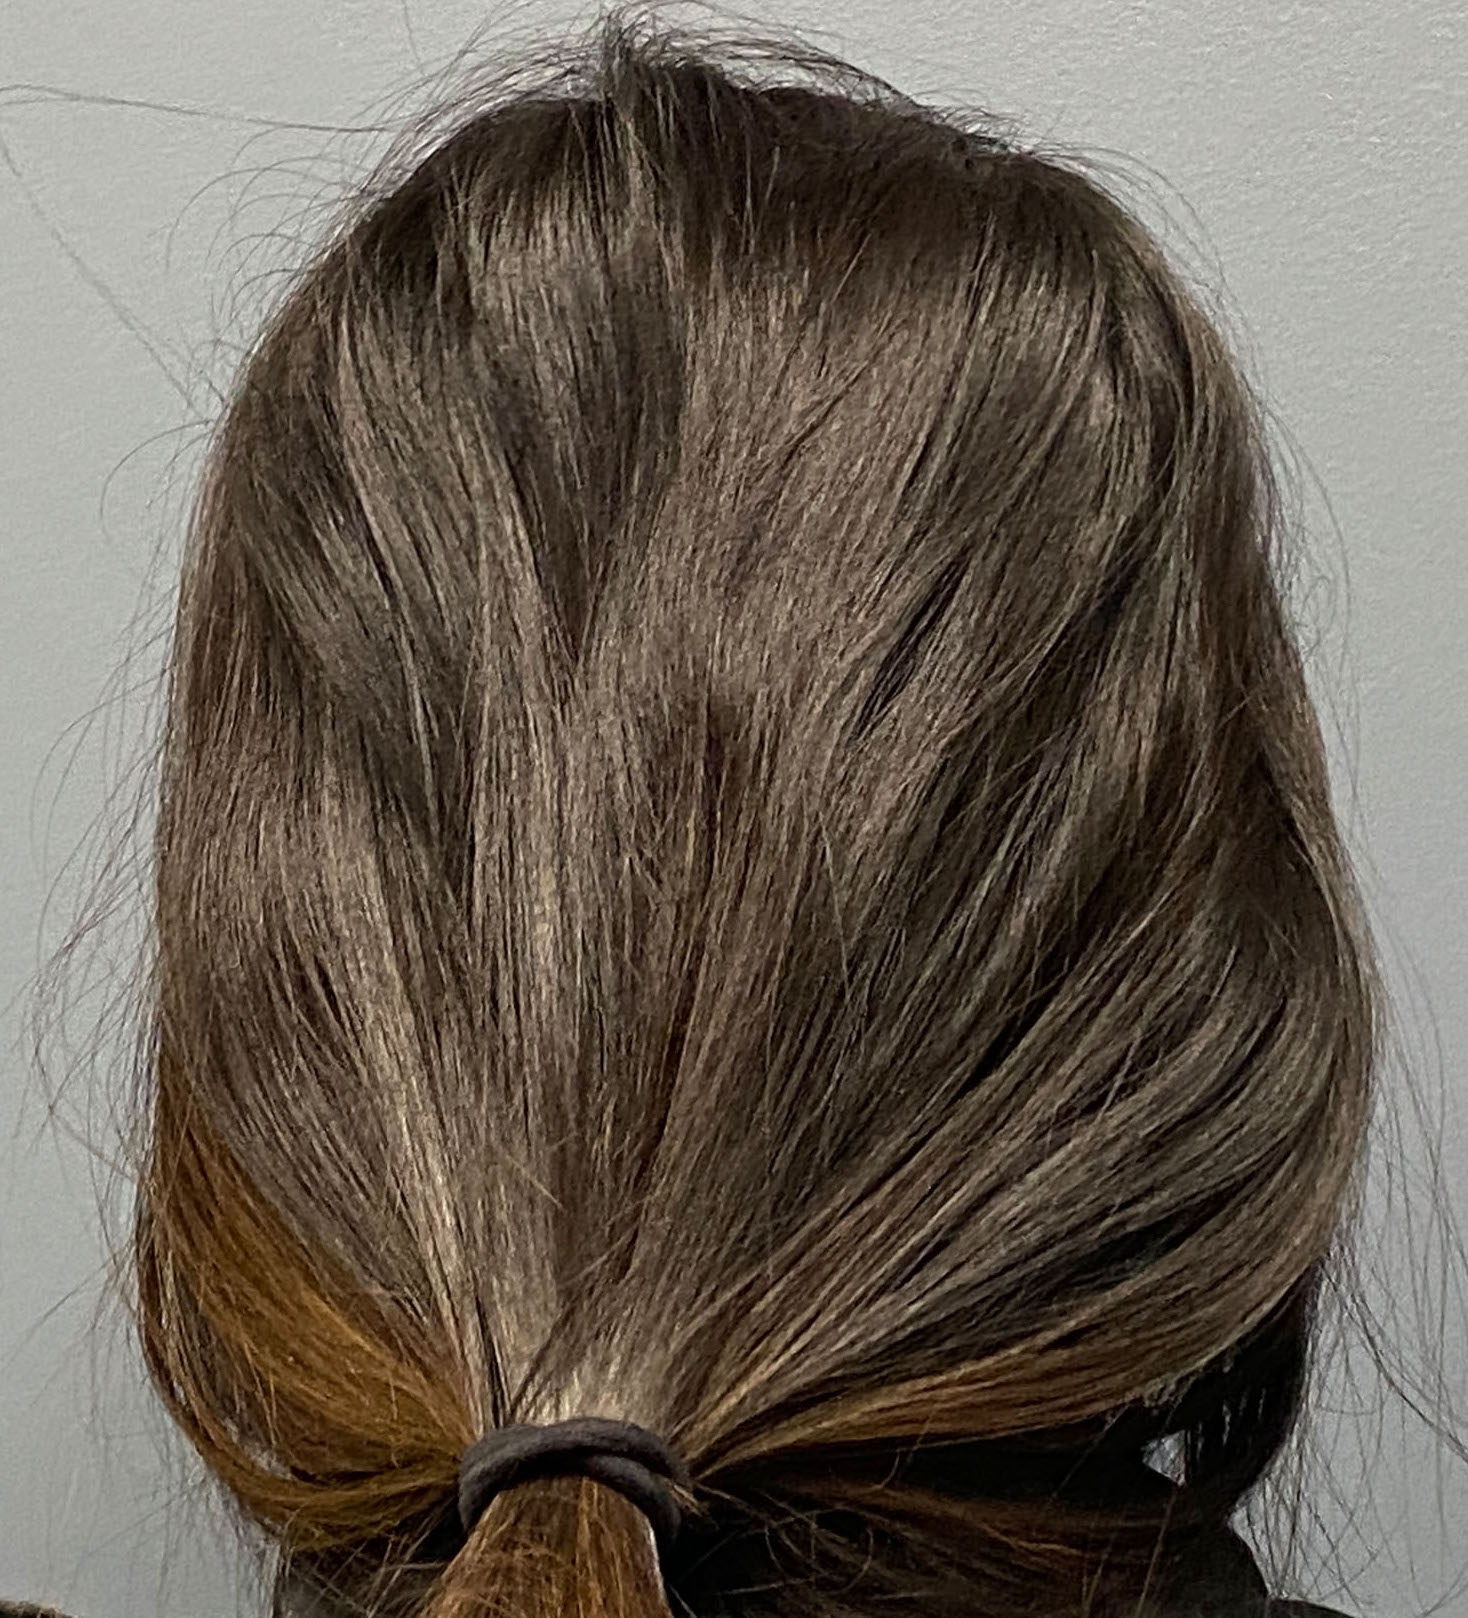

Long haired male with desire to augment a congenital flat back of the head.

Placement of custom back of head skull implant without trimming or shaving any hair. The incision was hard to find postop.

Long haired male with desire to augment a congenital flat back of the head.

Placement of custom back of head skull implant without trimming or shaving any hair. The incision was hard to find postop.